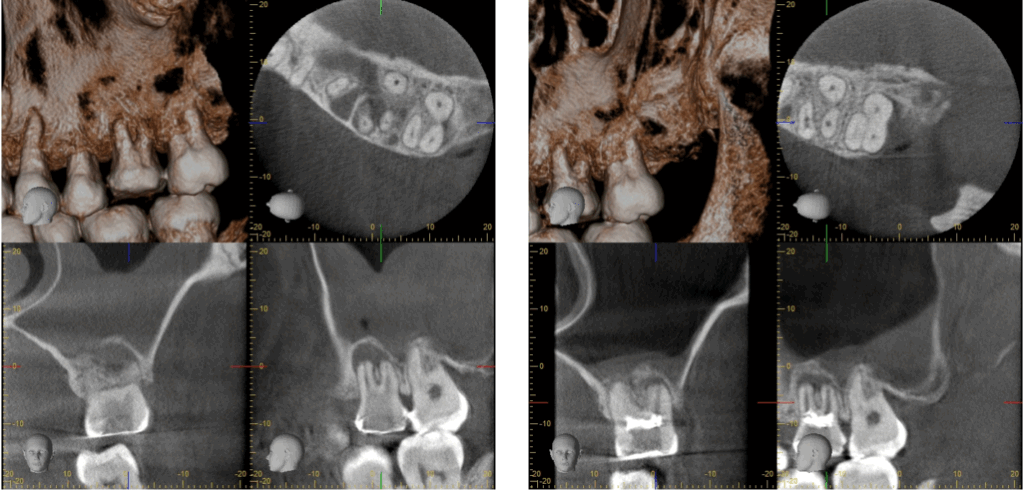

③CTによる精密診断

当院では、レントゲンだけでは見えない部分を確認するため、歯科用CTによる立体的な診断を行っています。

この方のCTを撮影したところ、根の先に明らかな炎症があり、その周囲の骨が吸収(溶解)していました。

さらに、上顎洞の粘膜が3〜4mm以上に肥厚しており、炎症が上顎洞内に及んでいる状態でした。

3か月後のCTでは、根の先の黒い影が小さくなり、炎症範囲が縮小していました。

さらに6か月後には、骨の欠損部分に新しい骨が再生している像が確認でき、上顎洞粘膜も正常な厚み(1mm以下)に回復していました。